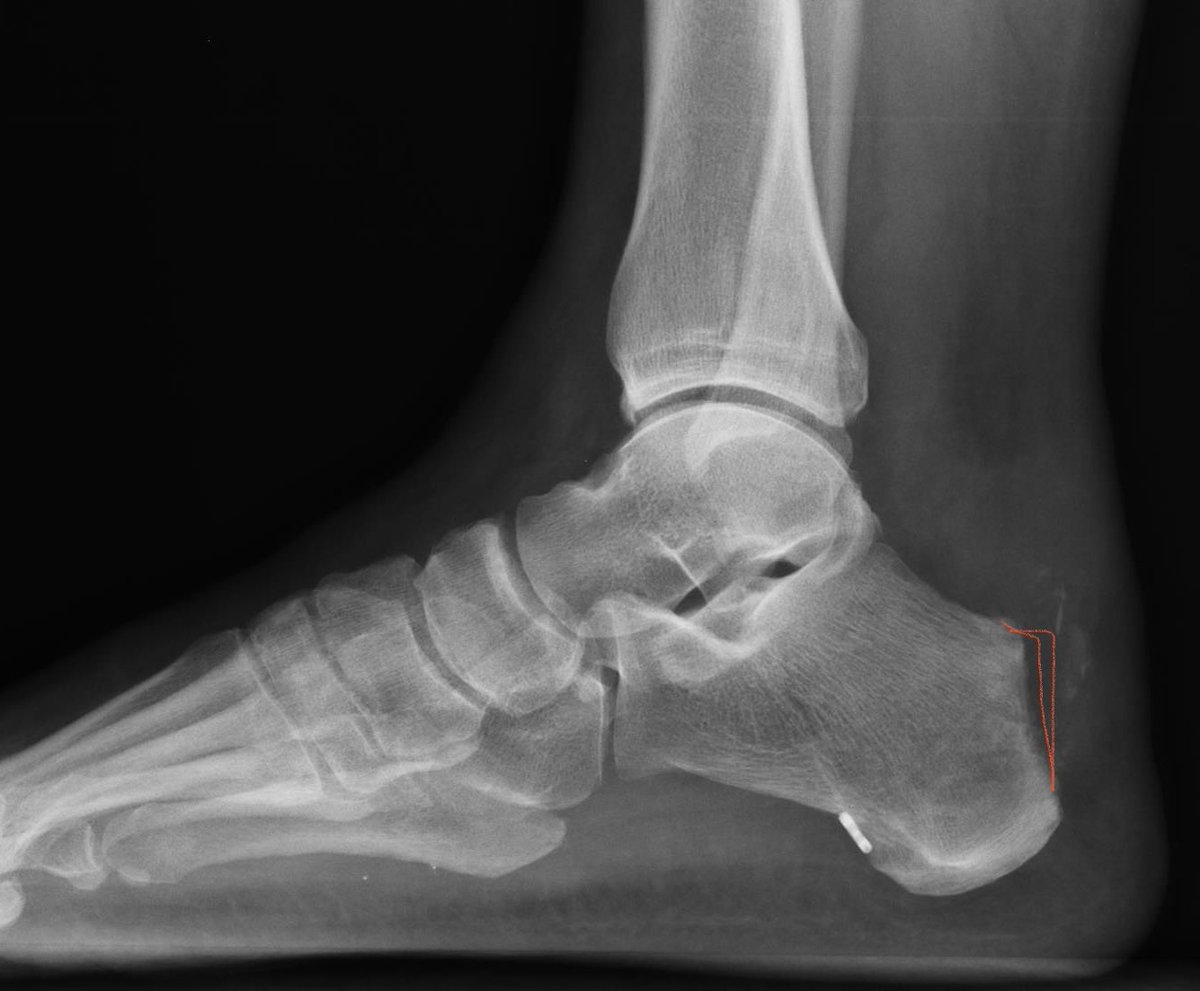

@FootAndAnkleMD @pratikorho @Footankledc @BostonFootAnkle @TheFootAnkleDoc @NaanDerthaal @natselrox @anilbhatortho @drmaniortho @DrJN_SportsMed I’m definitely interested in those less invasive techniques although I’m not sure how well I could adequately debride the diseased tendon. The postop lateral shows a fair amount of persistent intratendinous calcification.

@pratikorho @Footankledc @BostonFootAnkle @TheFootAnkleDoc @footankle @NaanDerthaal @natselrox @anilbhatortho @drmaniortho @DrJN_SportsMed In the presence of intra-tendinous disease, simple exostectomy is insufficient. Requires Achilles debridement, in this case, complete detachment, and repair. Can be done percutaneously. Endoscopic FHL added here as well (cortical button). Allows early WB and rehab.